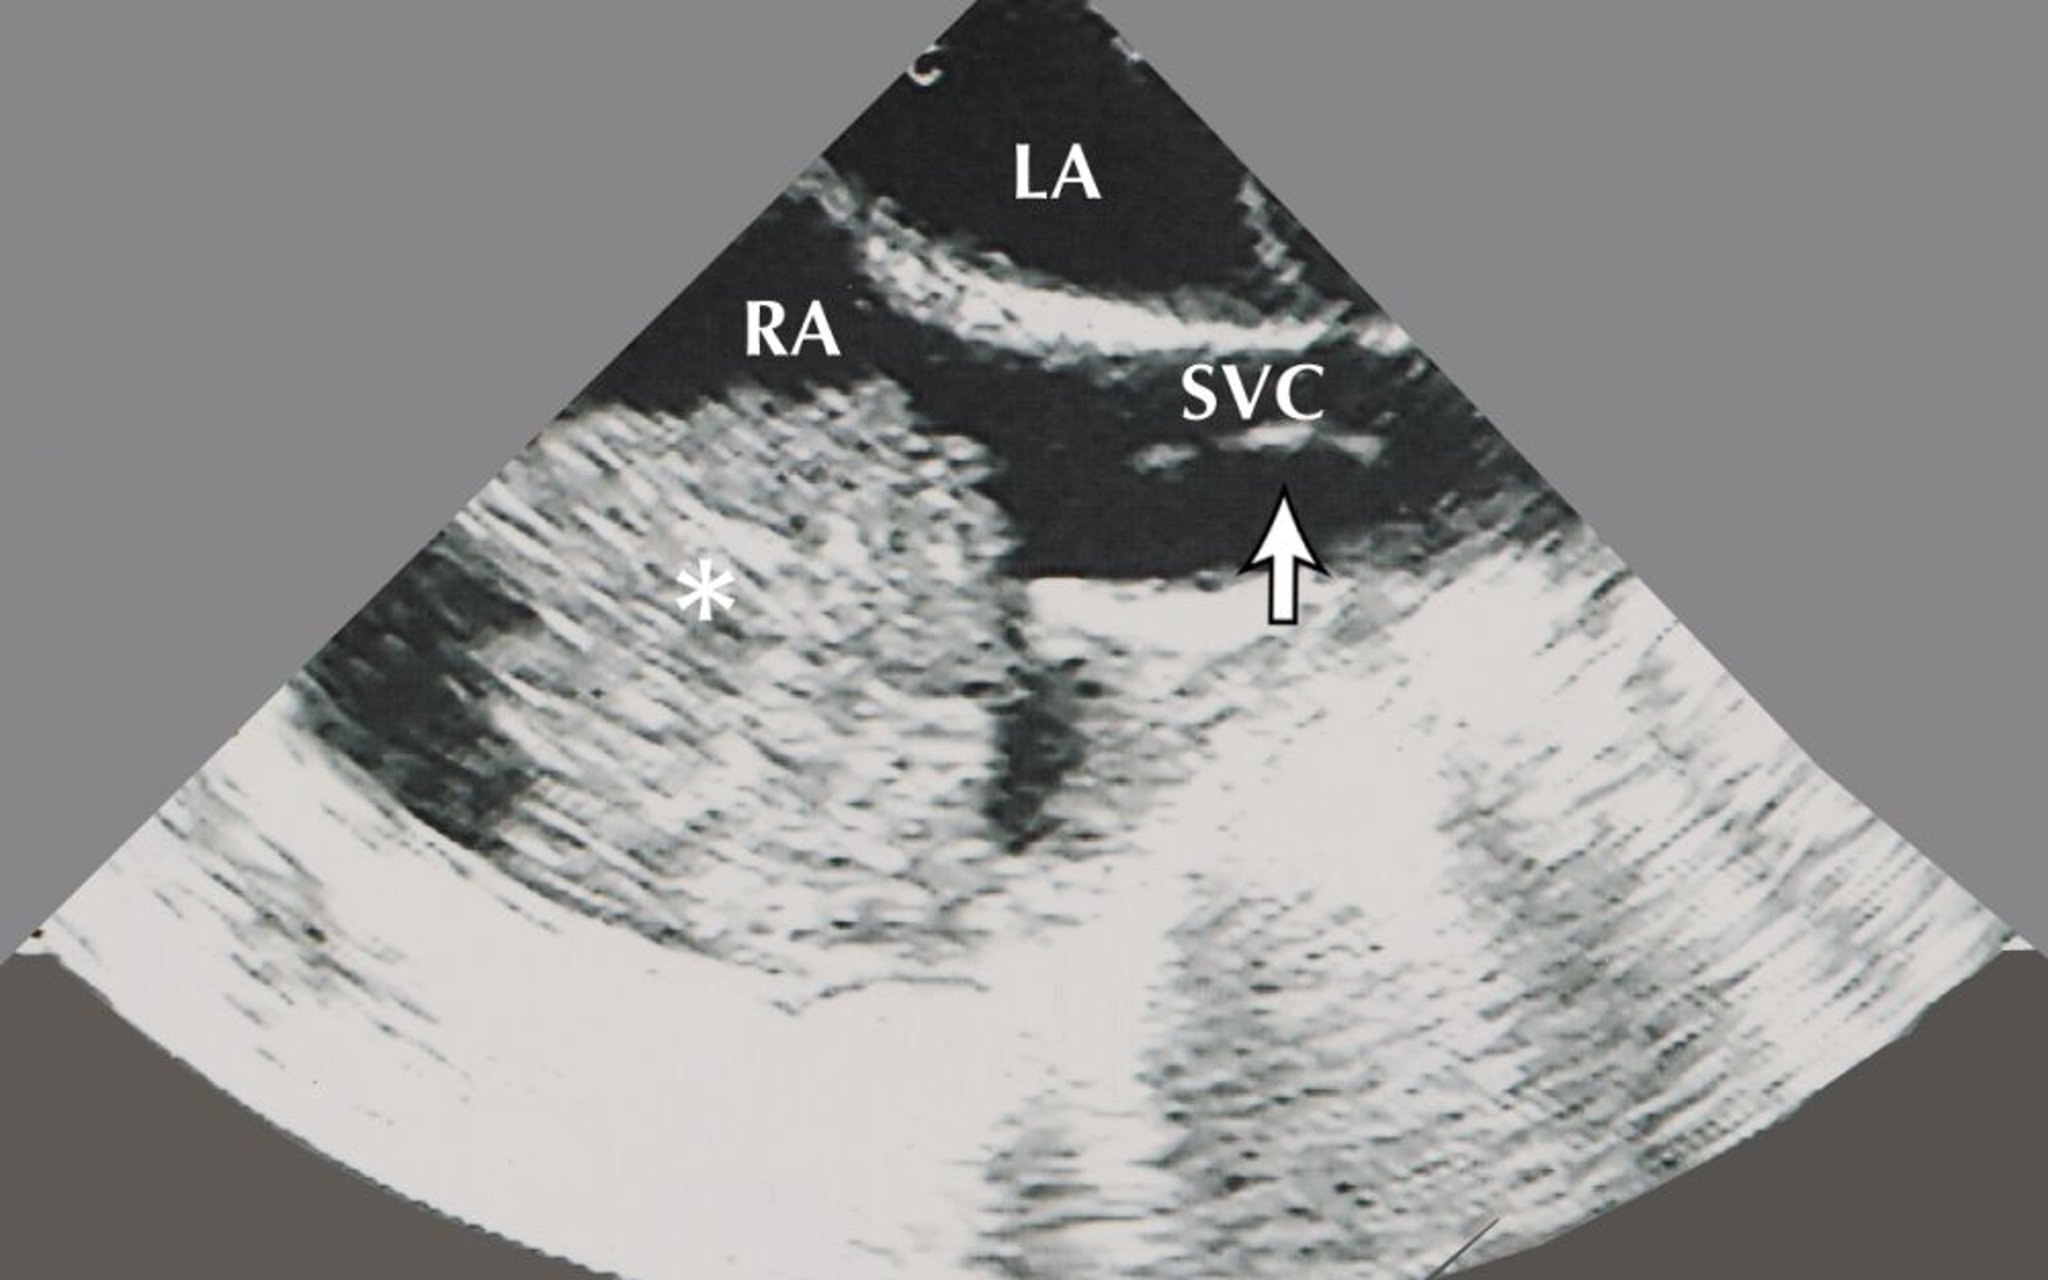

Atrial Myxoma (Echocardiogram)

This image shows an atrial myxoma (indicated by the asterisk) in the right atrium (RA). Also visible on this echocardiographic image are the left atrium (LA) and a biopsy bioptome (indicated by the arrow) in the superior vena cava (SVC).